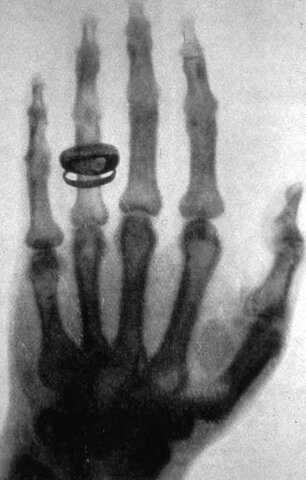

• Rayos X Wilhem Conrad Rontgen

Rayos X Wilhem Conrad Rontgen

Fue el propio Röntgen el que hizo la primera radiografía a la mano de su mujer quien, horrorizada por el resultado, se negó a participar en los estudios posteriores de su marido.